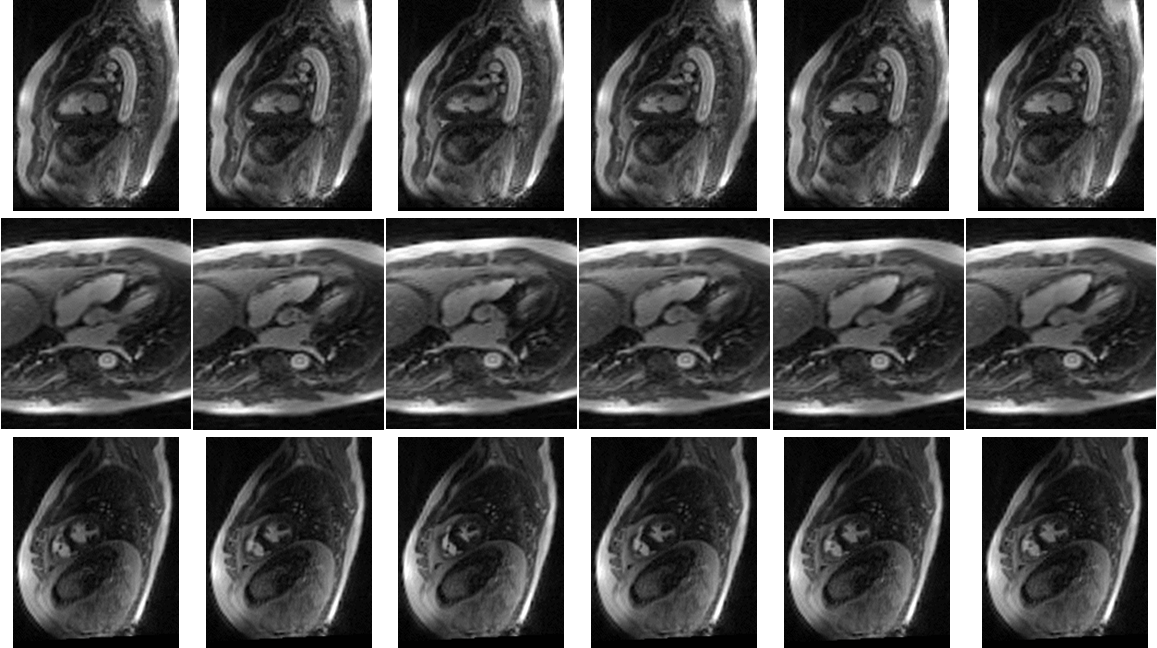

Figure 2. Reformatted long-axis views (first two rows) and short-axis view (third row) over one cardiac cycle, shown at the same temporal resolution as in Figure 1 (only 6 of the 12 reconstructed frames are shown). The reconstructed cine frames clearly demonstrate soft tissue contrast, including visualization of the papillary muscles and myocardium, while capturing free-breathing cardiac and respiratory motion.